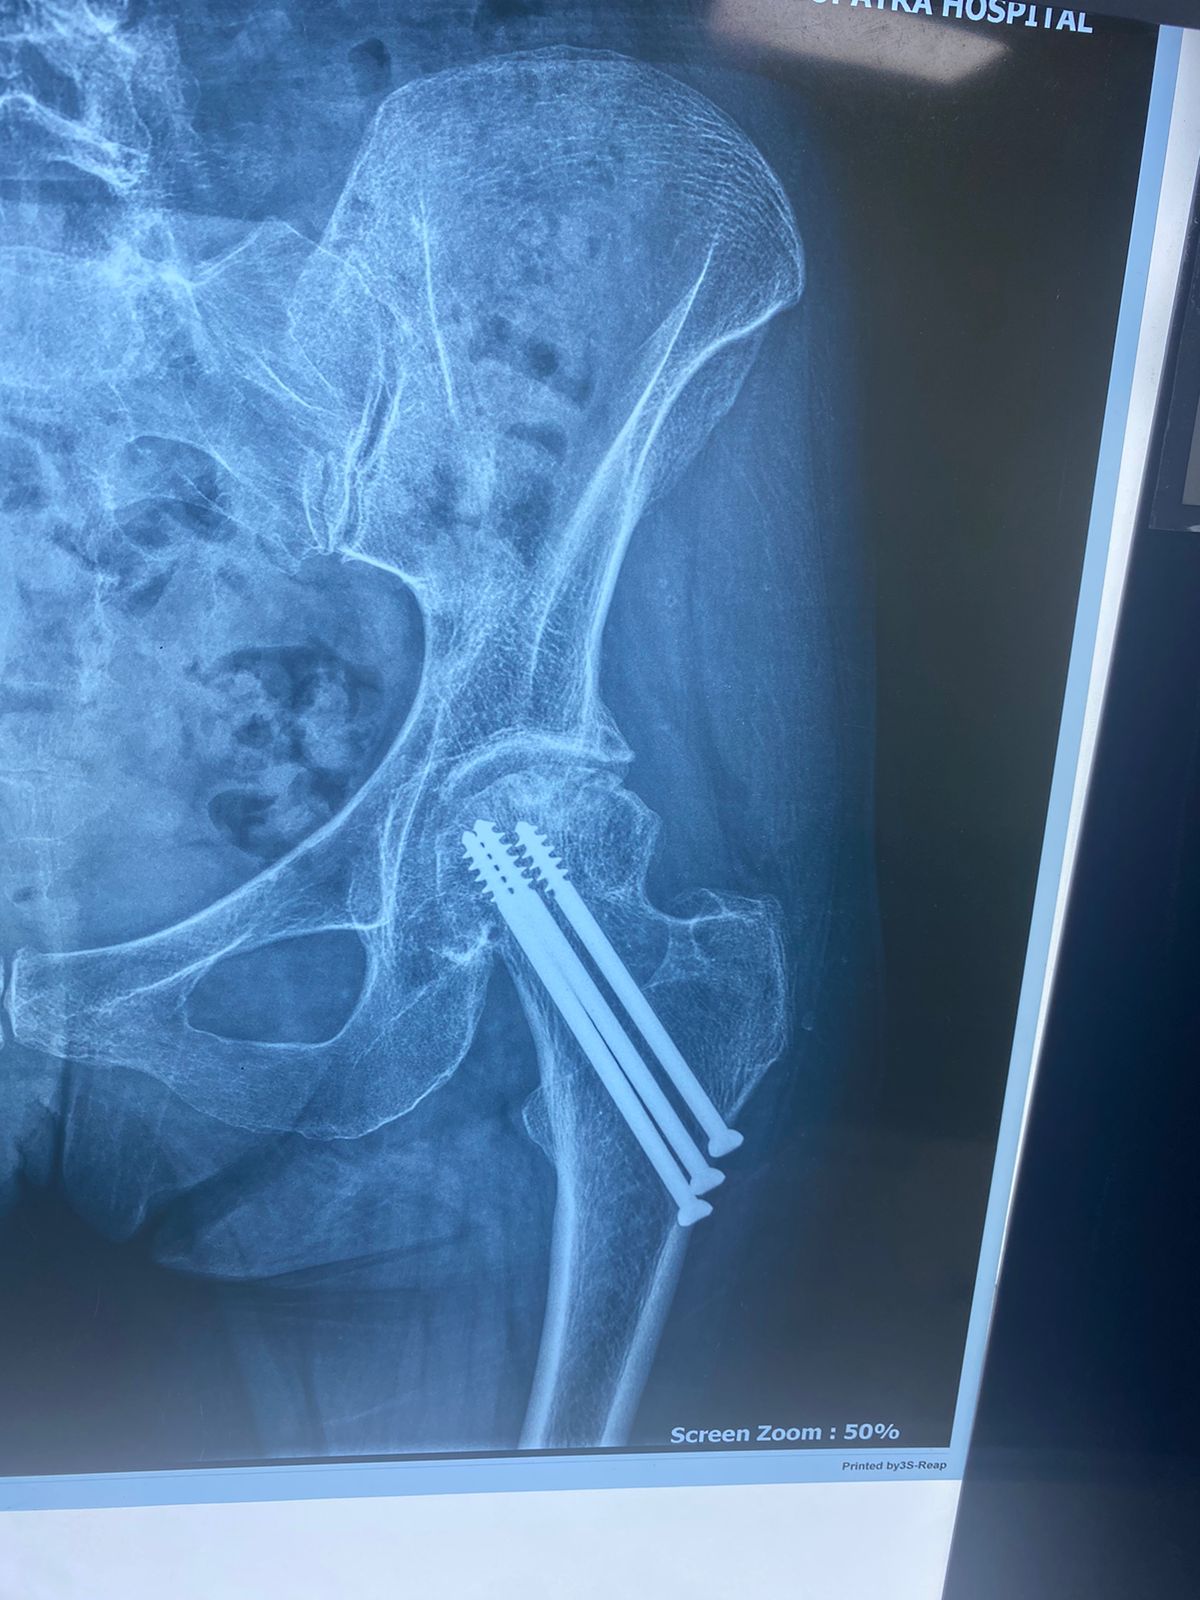

تم إجراء تثبيت داخلي لكسر بالحوض بمسامير عام ٢٠٠٩

في عام ٢٠٢١ بدأت تشعر بالام متزايدة بالمفصل كما بينت الاشعات تآكل به